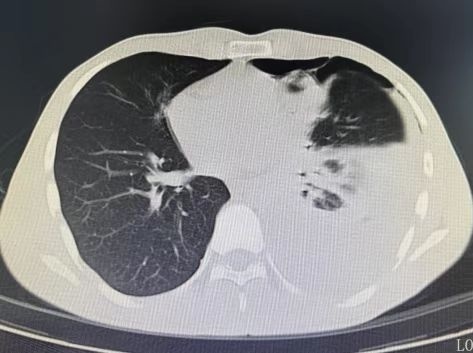

胸部CT检查结果让所有人警惕:小张左侧胸腔积聚大量浑浊积液,几乎占胸腔近三分之一,已压迫肺部引发气胸,不符合普通肺炎的影像学特征。当天,他就被收治入院。